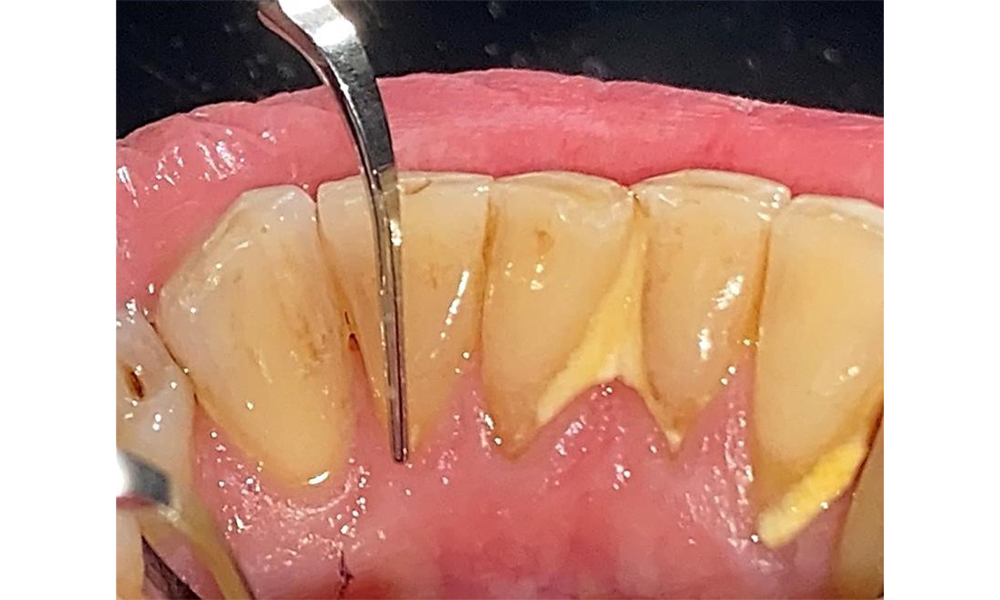

Der Patient pflegt mit Interdentalbürstchen und mit einer elektrischen Zahnbürste. Er zeigt eine gute Compliance und ein gutes häusliches Mundhygieneverhalten bzw. - verständnis. Eine regelmäßige Motivation und Reinstruktion sind aufgrund des Progressionsrisikos unerlässlich insbesondere der Interdentalraumpflege aufgrund der erhöhten Sondierungstiefen in diesen Bereichen. Es zeigen sich lokalisiert Zahnstein in der Unterkieferfront lingual und weiche Beläge, die dem Patienten aufzuzeigen sind. Ggf. müssen Interdentalbürstchen auf die Größe geprüft und angepasst werden. Ein weicher Bürstenaufsatz ist aufgrund der freiliegenden Wurzeloberfläche zu empfehlen, um keilförmigen Defekten vorzubeugen. Eine Zahnpasta mit einem niedrig abrasiven Wert sollte angewendet werden.

In der Instrumentierung sind bezüglich der Methodenwahl keine Einschränkungen gegeben. Aufgrund der parodontalen Vorerkrankung und dem hohen Rezidivrisikos ist die Vorbeugung einer Erkrankungsprogression durch die regelmäßige supra- und subgingivale Instrumentierung unerlässlich. Die Wahl der Instrumente zur mechanischen Biofilmentfernung ist aus allgemeingesundheitlicher Sicht nicht eingeschränkt und erfolgt bedarfsgerecht. Harte und mineralisierte Beläge wie Zahnstein und Konkremente sind mittels Handinstrumenten oder Schall/ Ultraschallscalern zu entfernen (Abb. 9) (8, 9).